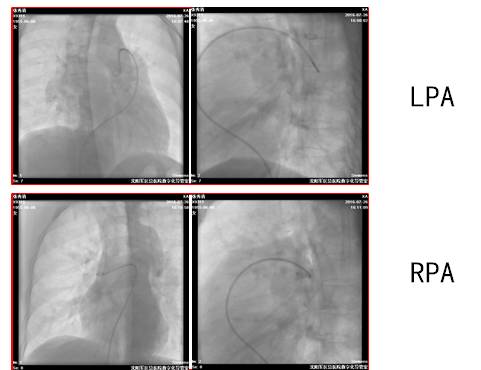

术前肺动脉造影结果

第1次术后肺动脉造影结果(1)

第1次术后肺动脉造影结果(2)